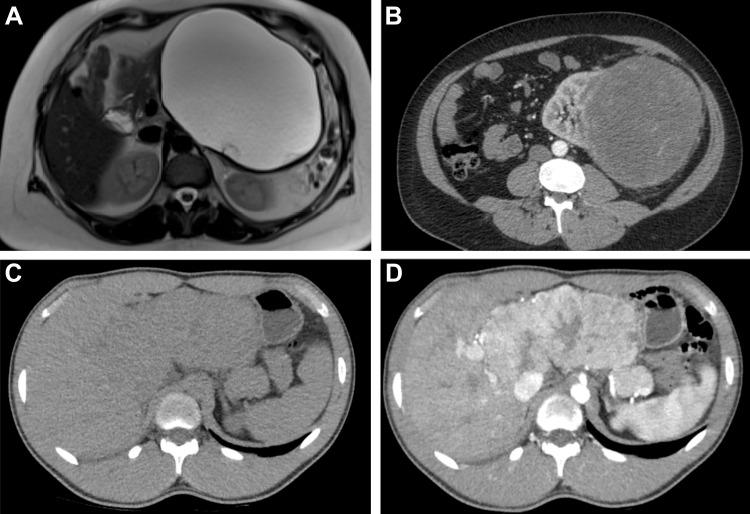

Radiomics refers to the extraction of mineable data from medical imaging and has been applied within oncology to improve diagnosis, prognostication, and clinical decision support, with the goal of delivering precision medicine. The authors provide a practical approach for successfully implementing a radiomic workflow from planning and conceptualization through manuscript writing. Applications in oncology typically are either classification tasks that involve computing the probability of a sample belonging to a category, such as benign versus malignant, or prediction of clinical events with a time-to-event analysis, such as overall survival. The radiomic workflow is multidisciplinary, involving radiologists and data and imaging scientists, and follows a stepwise process involving tumor segmentation, image preprocessing, feature extraction, model development, and validation. Images are curated and processed before segmentation, which can be performed on tumors, tumor subregions, or peritumoral zones. Extracted features typically describe the distribution of signal intensities and spatial relationship of pixels within a region of interest. To improve model performance and reduce overfitting, redundant and nonreproducible features are removed. Validation is essential to estimate model performance in new data and can be performed iteratively on samples of the dataset (cross-validation) or on a separate hold-out dataset by using internal or external data. A variety of noncommercial and commercial radiomic software applications can be used. Guidelines and artificial intelligence checklists are useful when planning and writing up radiomic studies. Although interest in the field continues to grow, radiologists should be familiar with potential pitfalls to ensure that meaningful conclusions can be drawn. Published under a CC BY 4.0 license.